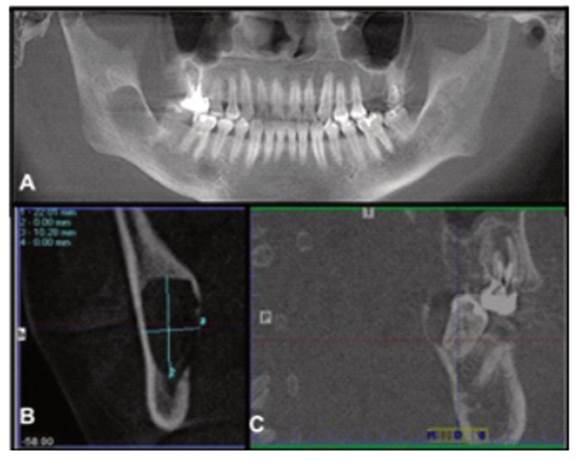

The general clinical examination revealed mild facial asymmetry with increased volume of the right posteroinferior hemiface, with effacement of the right nasolabial line, pain on deep palpation, and presence of crepitus, with no signs of inflammation or palpable lymph nodes (Fig. 1A).

The intraoral clinical examination revealed a slight increase in the volume of the vestibular mucosa of the lower right molar region without color alterations. We detected prominent superficial blood vessels, a slight expansion of the external cortex, crepitus, moderate pain on palpation, absence of tooth 4.8, increased sensitivity of tooth 4.7 to thermal tests, and a tingling sensation on vertical percussion. There was evidence of increased crepitus and pain radiating in a caudal direction on deep palpation of the right mandibular ramus on its inner side. (Fig. 1B).

The panoramic radiograph shows a large unilocular and radiolucent lesion measuring approximately 5x4 cm, with defined borders, corticated edges, projecting distally from the root of tooth 4.7, extending in the cephalic direction until roughly the middle of the mandibular ramus. Its growth compromises tooth 4.7, the posterior region of the mandibular body, and right mandibular ramus and angle. Tooth 4.8 is absent, and there is a slight caudal displacement of the mandibular canal.

The CBCT, in its panoramic reconstruction (Fig. 2A), confirms an extensive hypodense lesion with defined and corticated borders involving the root of tooth 4.7. The transverse reconstruction shows a 22.01x10.28 mm oval lesion, with cortical expansion and severe thinning with perforation of the lingual cortex (Fig. 2B). The sagittal reconstruction shows exposure of the distal and palatal region of tooth 4.7 with complete alveolar bone resorption. We also detected a slight displacement of the mandibular canal in the caudal direction (Fig. 2C).